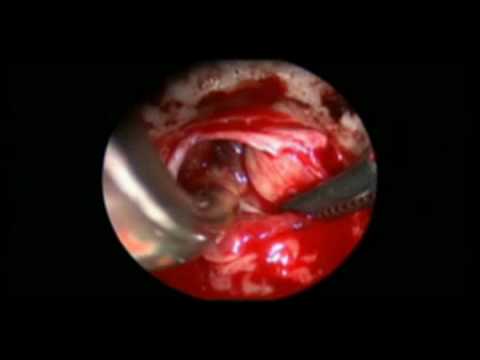

Dekompresja mikronaczyniowa - leczenie neuralgii...

Na filmie zaprezentowano mikronaczyniowe odbarczenie zastosowane w leczeniu neuralgii nerwu trójdzielnego. Zaprezentowany przypadek dotyczy pacjentki ze zdwojoną tętnicą móżdżkową górną. Jedna z tętnic...